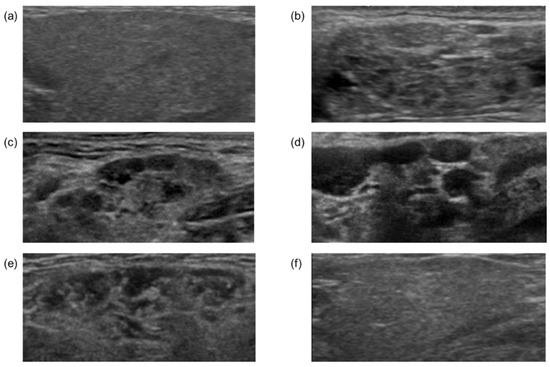

3.1. Patient Characteristics and Classification of US Findings in Submandibular Glands